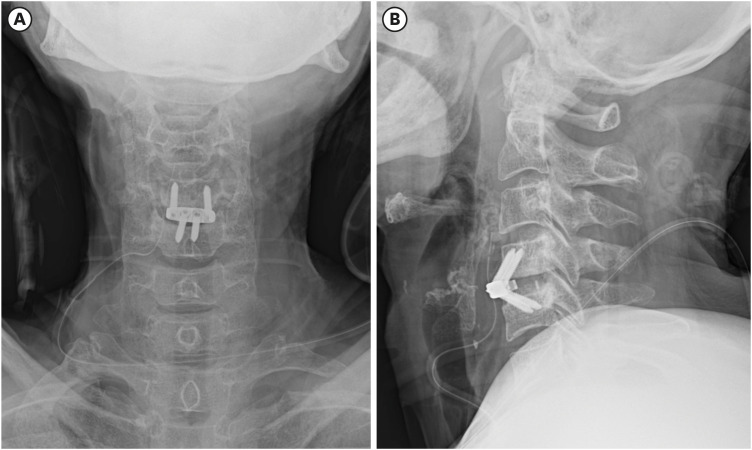

虽然颈椎椎间盘切除前路融合术(ACDF)是治疗颈椎病最常见的手术之一,但它也与各种术后并发症有关。食管穿孔是一种罕见但非常严重的 ACDF 术后并发症,而螺钉从口腔挤出的病例则更为罕见。在此,我们介绍了一名 61 岁女性的病例,她在接受 ACDF 手术 6 个月后因螺钉从口腔挤出而到我们的急诊中心就诊。虽然影像诊断没有证实食管穿孔,但螺钉经口挤出是并发症的明显证据。据我们所知,这是第一例未确诊食管损伤的口腔螺钉挤出病例。该病例表明,螺钉移位和食管穿孔的发生取决于患者的基础情况,如果症状轻微,仅靠保守治疗可能就足以治疗穿孔。

Although anterior cervical discectomy and fusion (ACDF) is one of the most common surgical procedures performed for the treatment of cervical disease, it is associated with a variety of postoperative complications. Esophageal perforation is a rare but very serious post-ACDF complication, and cases in which screws extrude through the mouth are even rarer. Herein, we present the case of a 61-year-old woman who visited our emergency center with oral extrusion of a screw 6 months after undergoing ACDF. Although diagnostic imaging did not confirm esophageal perforation, the oral extrusion of the screw was clear evidence of the complication. To the best of our knowledge, this is the first reported case of oral screw extrusion without confirmed esophageal injury. This case suggests that screw migration and esophageal perforation can occur depending on the patient's underlying condition, and if the symptoms are mild, conservative treatment alone may be sufficient to treat the perforation.